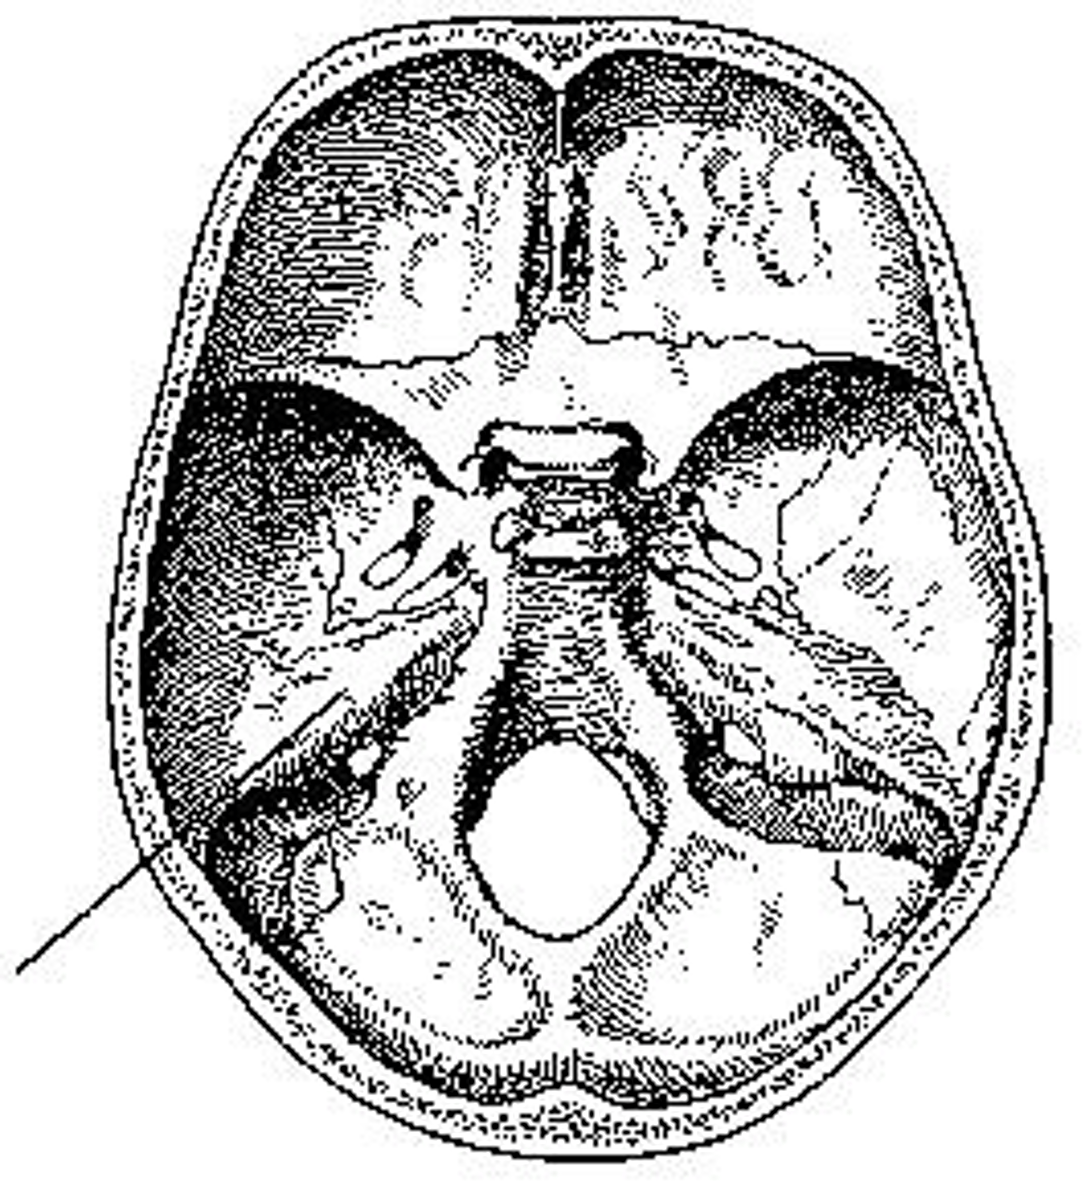

What part of the sphenoid is identified?

sella turcica

What part of the cranial base is identified?

petrous portion